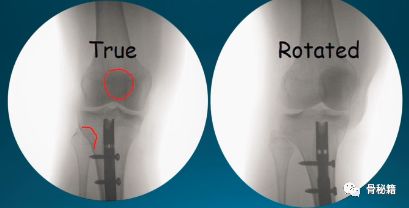

要想得到一个好的进针点,第一点就是有一个好的透视像,下肢的旋转要控制好,胫骨腓骨稍微重叠一部分,髌骨位于股骨髁的中央,即髌骨朝天。

下图为例,防止骨折向右侧移位,置于左侧阻挡钉。注意!植入阻挡钉后,需要重新扩髓!

在进针的时候,也需要进行阻挡植入阻挡钉,近端主要是后方和侧方有时候都需要